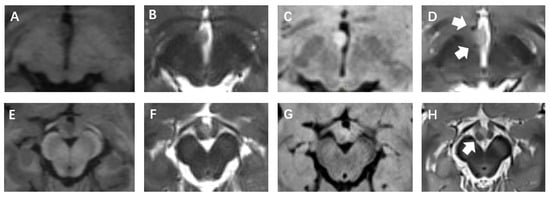

2.2. Surgical Procedure